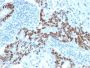

Positive Control

HeLa cells. Colorectal or Ovarian Carcinoma.

IHC (FFPE) (verified)

Higher concentration may be required for direct detection using primary antibody conjugates than for indirect detection with secondary antibody|Immunohistology (formalin): 1-2 ug/mL for 30 minutes at RT|Staining of formalin-fixed tissues requires boiling tissue sections in 10 mM citrate buffer, pH 6.0, for 10-20 minutes followed by cooling at RT for 20 minutes|Optimal dilution for a specific application should be determined by user